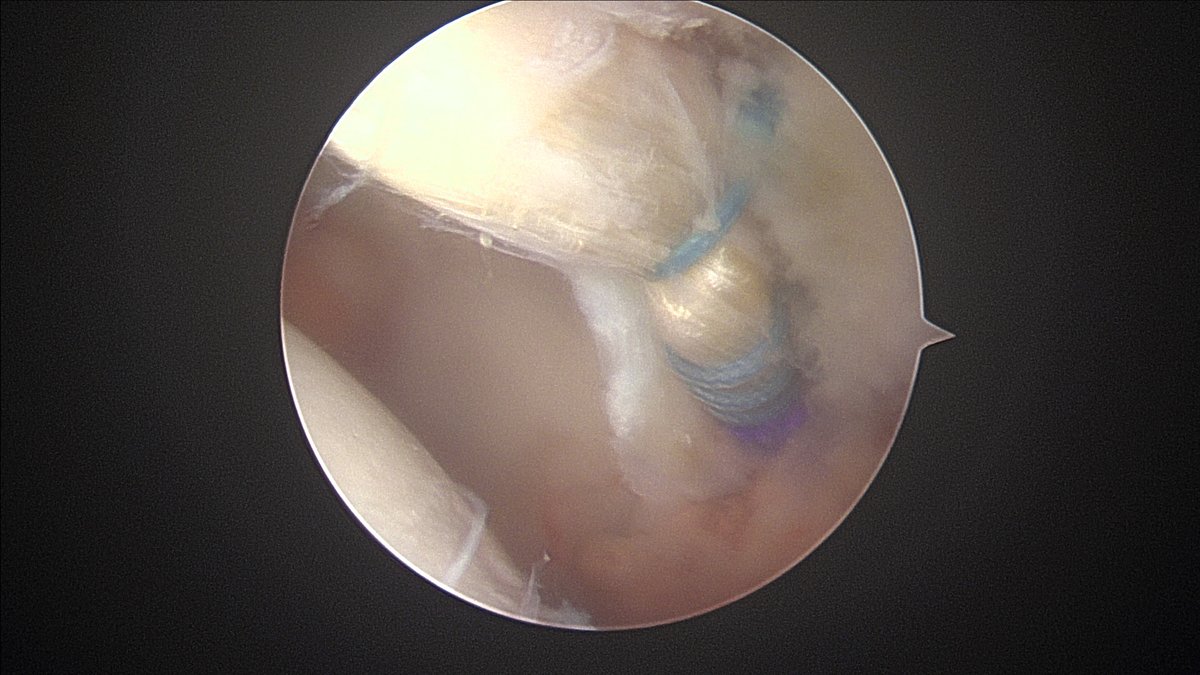

Want to know how I get from ๐คฌ-->๐ค? I'll be giving a presentation on my technique for #HipArthroscopy labral reconstruction at OSET in Las Vegas 9/21-9/23. Orthopaedic Summit

Did a #HipArthroscopy on a patient 15 years ago. Now, other hip is symptomatic with FAI. The discussion made me realize how much my rehab program has evolved over time. I'll be giving a talk Orthopaedic Summit this week. Biggest change: nearly all are weight bearing as tolerated.